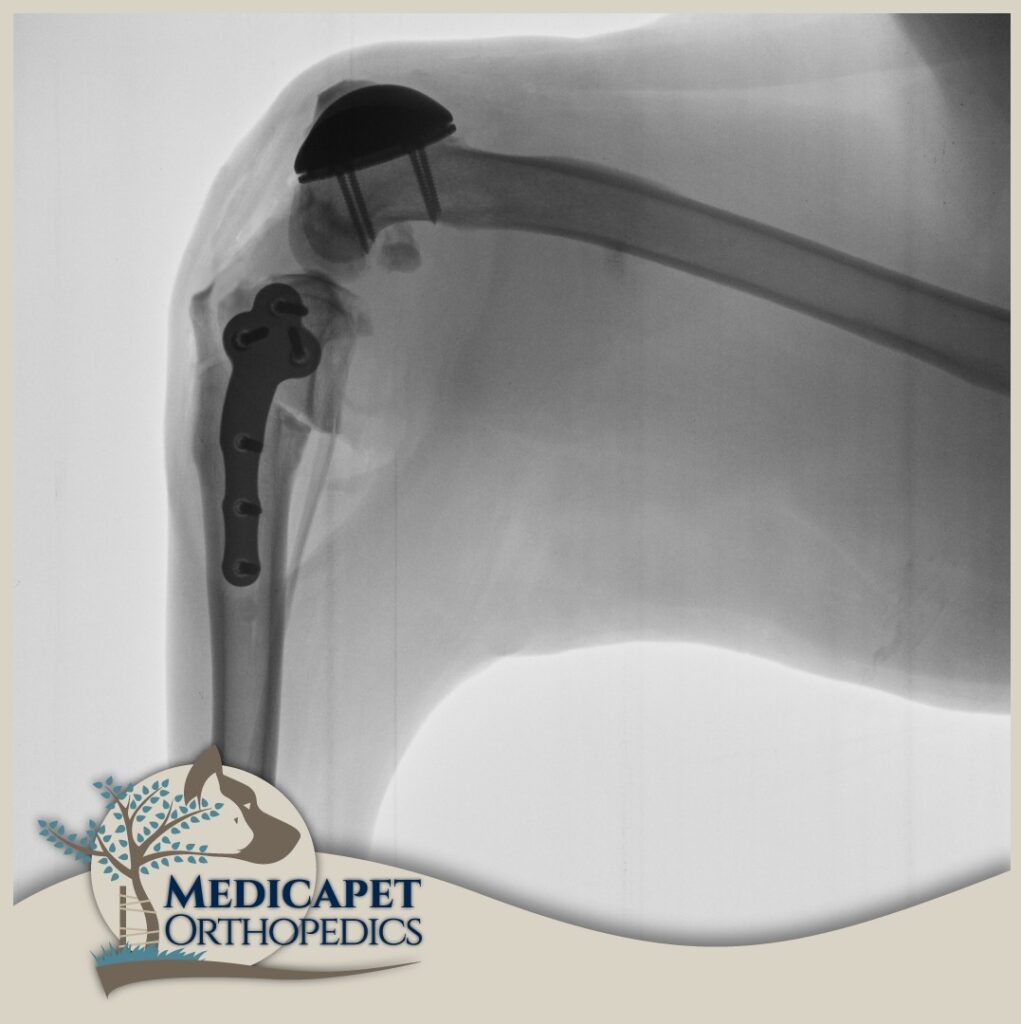

En Güncel Teknikleri Uyguluyoruz.

Her zaman eksiksiz donanım ve ekipman ile ameliyathanemizi hazır tutuyor, veteriner ortopedi ve nöroşiruji alanında dünyadaki son gelişme ve teknikleri sıkı sıkıya takip ederek en yeni implant skalalarını merkezimizde hazır bulunduruyoruz. İzmir’de ve Bölgemizde ilkleri gerçekleştirmekten dolayı gururluyuz.